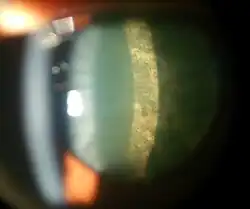

| Magnified view of a cataract seen on examination with a slit lamp | |

Nuclear sclerosis is the most common type of cataract, and involves the central or 'nuclear' part of the lens. This eventually becomes hard, or 'sclerotic', due to condensation on the lens nucleus and the deposition of brown pigment within the lens. In its advanced stages, it is called a brunescent cataract. In early stages, an increase in sclerosis may cause an increase in refractive index of the lens.[47] This causes a myopic shift (lenticular shift) that decreases hyperopia and enables presbyopic patients to see at near without reading glasses. This is only temporary and is called second sight.[48]